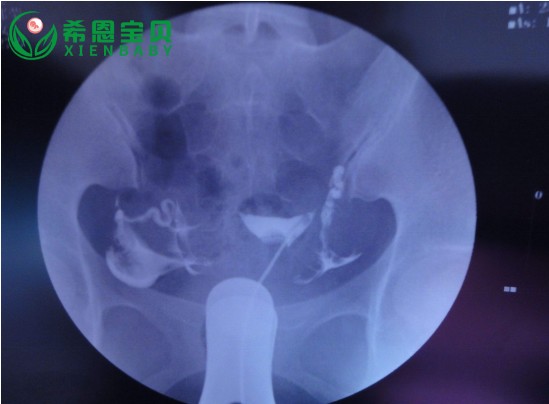

首先,我们来了解一下什么是子宫输卵管造影。简单来说,子宫输卵管造影就是通过向子宫输卵管内注入造影剂,并利用X线等成像技术观察其流动情况,以评估输卵管是否通畅的一项检查。

那么,为什么在做试管婴儿前检查中要进行子宫输卵管造影呢?这是因为,输卵管是女性生殖系统中非常重要的一部分,它连接着卵巢和子宫,是卵子在体内运动的通道。如果输卵管堵塞或者存在其他问题,那么就会导致卵子无法顺利地到达子宫,从而影响受孕。因此,在进行试管婴儿前检查时,必须先进行子宫输卵管造影,以确保输卵管通畅。

除了可以评估输卵管是否通畅外,子宫输卵管造影还有很多其他的优点。比如说,它可以帮助医生发现一些患者可能存在的疾病,如子宫肌瘤、腺肌症等。同时,它还可以帮助医生判断输卵管是否与其他器官粘连,并对不孕症进行初步筛查。